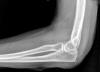

Fractura de olécranon con osteosíntesis.